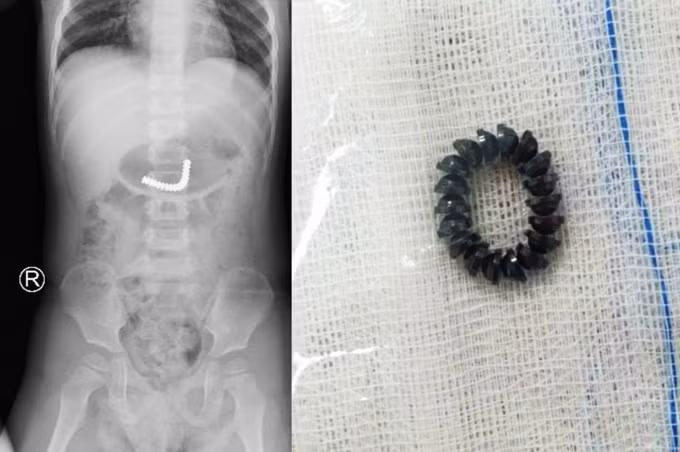

Ngày 22/12, Bệnh viện Nhi đồng Thành phố (TP.HCM) cho biết, vừa phẫu thuật cắt nối ruột thành công cho bé trai T.T.H.S. (34 tháng, ngụ quận 8, TP.HCM) vì nuốt tới những 18 viên nam châm từ máy massage mắt của mẹ.

Trước đó, bé S cầm máy massage mắt của mẹ chơi và nuốt hết 18 viên bi nam châm vào bụng. Khi nhập viện, các bác sĩ nhanh chóng cho bé chụp X-quang và phát hiện dị vật trong dạ dày. Ngay sau đó, dị vật đã di chuyển xuống ruột non, cháu bé được các bác sĩ chỉ định nội soi tiêu hoá khẩn.

Trong khoảnh khắc này, các bác sĩ khoa Ngoại Tổng hợp quyết định khẩn trương mổ nội soi thám sát ổ bụng. Ê kíp mổ nhẹ nhàng mở vết mổ ngay rốn và đưa đoạn ruột phình chứa dị vật đến khu vực mổ. Sau khi đoạn ruột được mở hỗng tràng, các bác sĩ tiến hành lấy ra 18 viên nam châm dính kết chùm lại.

Bé trai được các bác sĩ tiến hành phẫu thuật lấy dị vật.